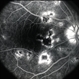

- multifocal choroiditis, posterior segment inflammation, white dot syndrome

- late-phase FA showing arteriolar attenuation and late staining of choroidal lesions